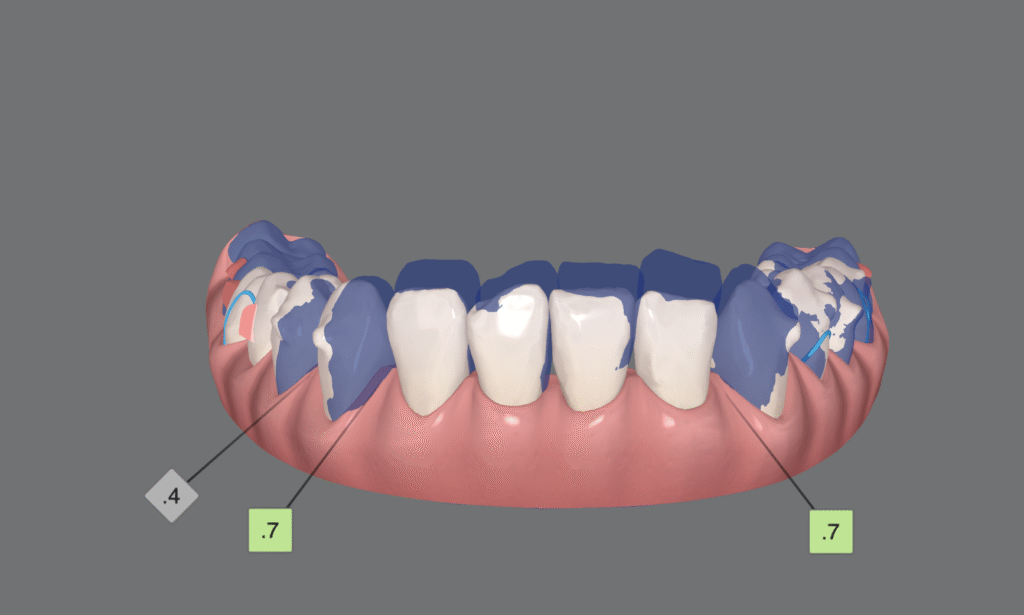

Además de esto, planificar la intrusión con espacios interdentales de 0,1 o 0,2mm reduce la fricción entre las piezas y mejora los resultados de manera sencilla, sobre todo en casos en los que hemos planificado stripping, el cual no siempre realizamos con una precisión del 100%.